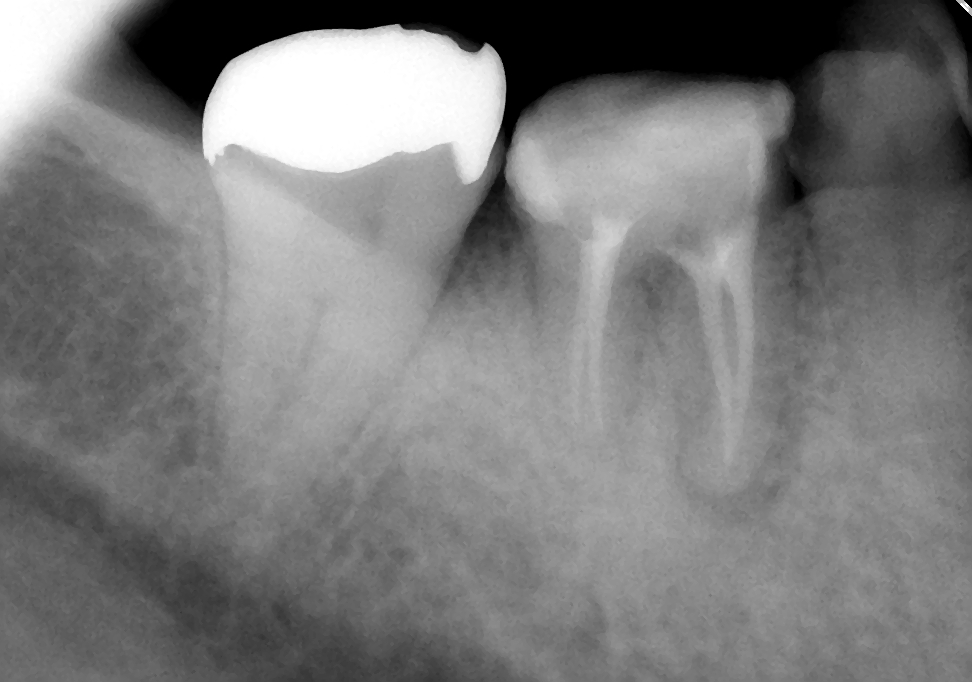

↑7ヵ月後

初診時に溶けていた骨もだいぶ再生されてきました。7ヶ月間症状も特になく、気にすることなく左右バランスよく咬めるとの事。ということで、主治医の先生でかぶせ物を入れてもらうことにしました。まずは一安心(^o^)